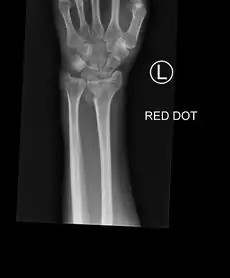

![]() | |

| An X-ray showing a Colles' fracture | |